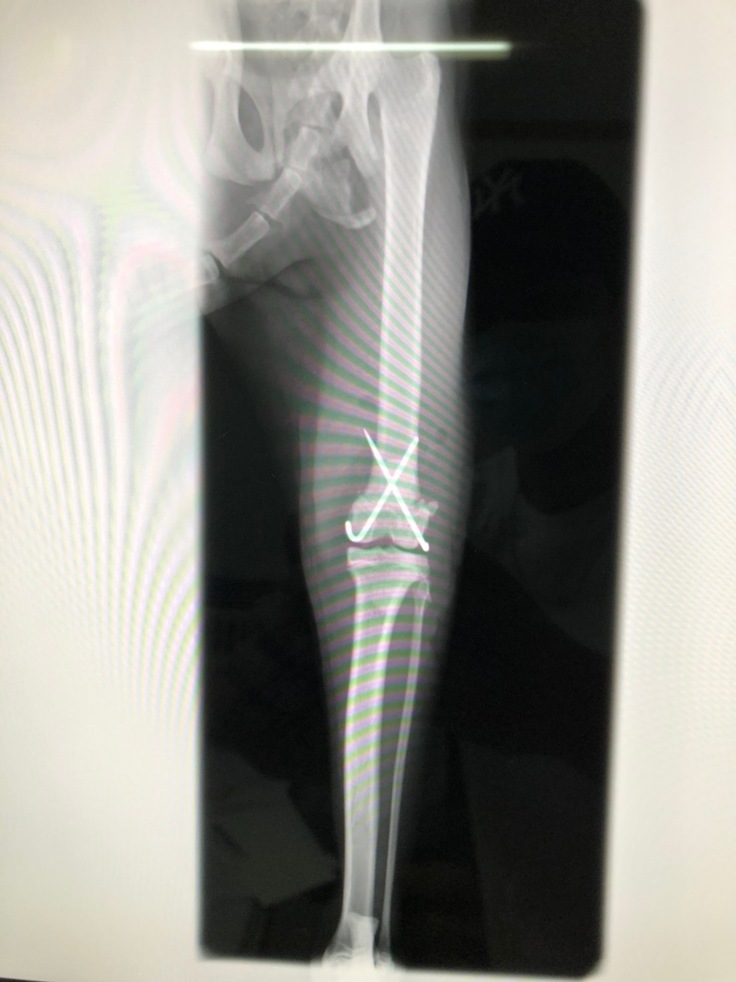

クロスピン固定手術後のレントゲン

左大腿骨遠位骨端板骨折のクロスピン除去手術 30,000円

7月下旬にクロスピン除去手術予定

左大腿骨遠位骨端板骨折に対してクロスピン固定、子宮卵巣摘出手術